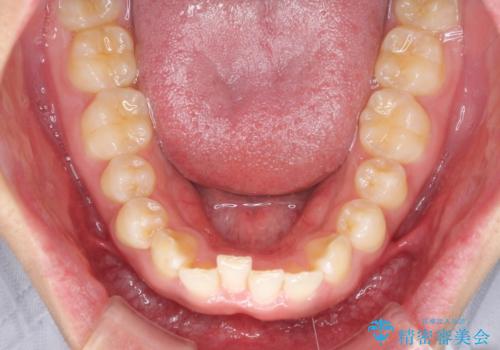

- 前歯のデコボコや隙間と深い咬み合わせ(ディープバイト)を気にして来院された患者様です。

インビザラインによる上下歯列の側方拡大と後方移動、IPR(歯と歯の間を削る)にるスペースの獲得により、デコボコとディープバイトを改善することとしました。

気になっていたデコボコや隙間は改善し、きれいな歯列に整えることができました。